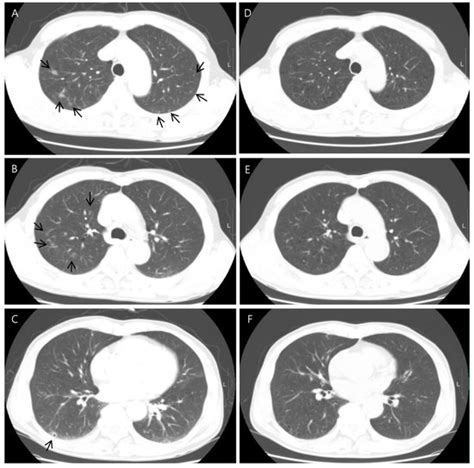

Cryptogenic Organizing Pneumonia: Evolution of Morphological Patterns ...

mdpi.com